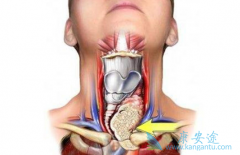

放射性碘难治性 DTC(RAI-DTC)患者预后较差,是目前甲状腺癌诊疗领域的难题,而靶向药物的出现为 RAI-DTC 治疗带来了新的契机。2017 年 3 月, 多吉美 (索拉非尼)获批甲状腺癌适应症,是目前中国唯一治疗放射性碘难治性分化型甲状腺癌的靶向药物。索 ...